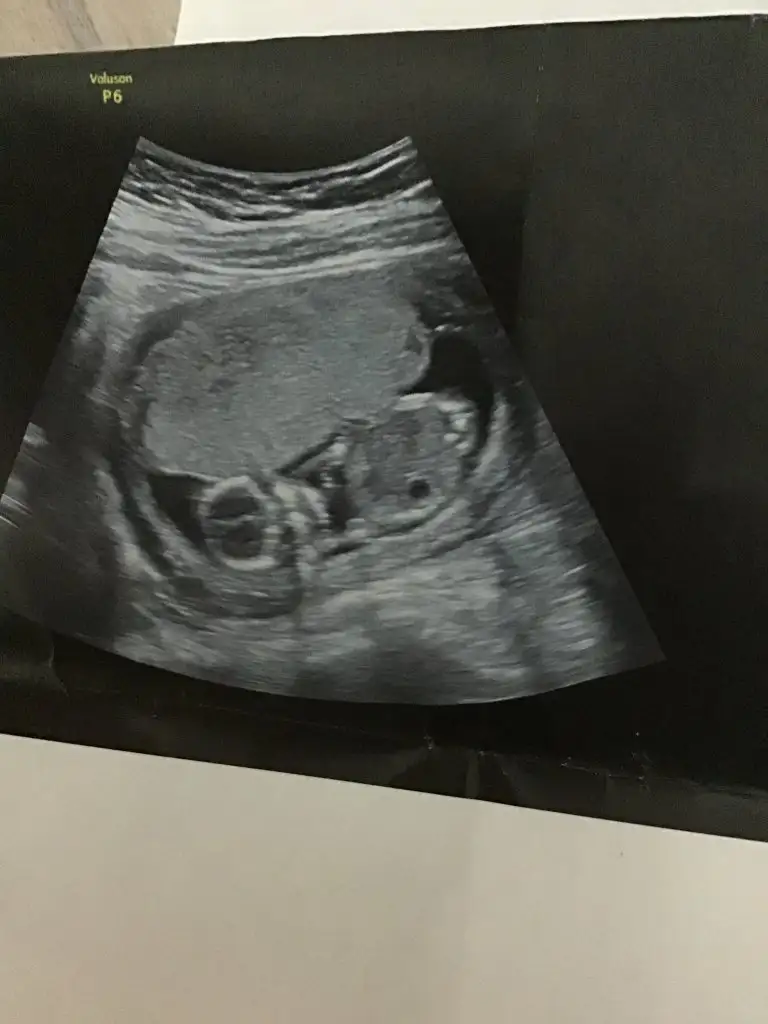

Karindan ise erkek vajinal ise kiz

Erkek karındansa değilse kızbu da benim 6+6 hali :)

Tam ortada o yüzden yorum yapamıyorum :) ama yinede söyle birşey dersen erkek gibi karındansaBu benım 7 haftalık kesem canım bakabilir mısın

Evet karından canimTam ortada o yüzden yorum yapamıyorum :) ama yinede söyle birşey dersen erkek gibi karındansa

benim bebeğimde tahminde bulunur musunuz 12 haftalıklenki usgsiNet değil usg erkek olabilir

bunada bakabilmisiniz 12+4 de çekilenKese %75 nub %85 en iyi nub tahmini onun için 11 12 13 haftalar olmalı